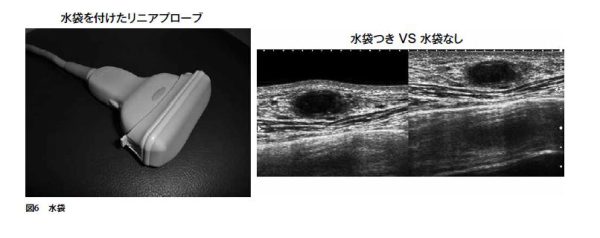

鮮明な画像を得るための工夫として、乳腺や表在領域の検査には、プローブにアタッチメント式の水袋を装着して使用している。アナログ装置の時代には、キテコ(半固形状伝達媒質)を使用した思い出もあるが、利便性は比較にならない。

プローブと体表との密着を良くし、アーチファクトの軽減、コントラストの向上がみられ鮮明な画像が得られる(図6)。